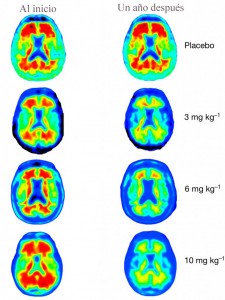

En el transcurso de un año, y en los primeros datos de la fase 1 de los ensayos, los investigadores dieron inyecciones mensuales de aducanumab a 165 personas en dosis de 1, 3, 6 o 10 mg / kg. Los incluidos en el ensayo o bien tenían un diagnóstico de Alzheimer leve o tenían problemas de memoria temprana y evidencia de altos niveles de la proteína beta- amiloide. Los participantes se sometieron a escáneres cerebrales, análisis de sangre y fueron evaluados por su memoria y habilidades cognitivas durante el estudio. Los investigadores encontraron en los escáneres cerebrales que aducanumab reduce los niveles de amiloide, con la dosis máxima de 10 mg / kg que era las que parecían mostrar un mayor efecto en la limpieza de las placas.

Imágen: Sevigny/Nature